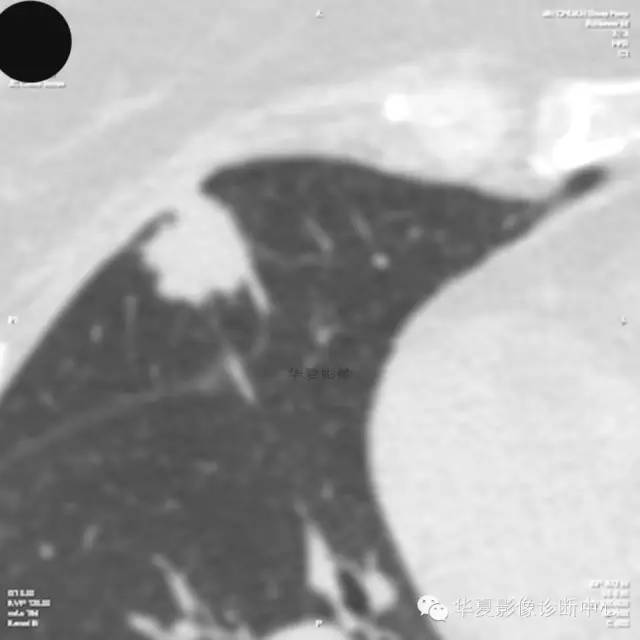

【病例学习】典型周围型肺癌CT病例一例

女,56岁,其父因肺癌去世,自觉胸部疼痛不适来诊要求拍胸片。

1.右肺上叶:肺组织1块,大小13×4×7cm。切面棕红色。2.右肺上叶肿物:灰白色组织一块,大小3×1×1.5cm。切面灰白色。3.右肺中叶结节:灰白色绿豆大组织1块。4.淋巴结:灰黑色绿豆大组织1块。

(右)肺中分化鳞状细胞癌。浸及胸膜。支气管残端切净。淋巴结未见癌转移(0/10)。